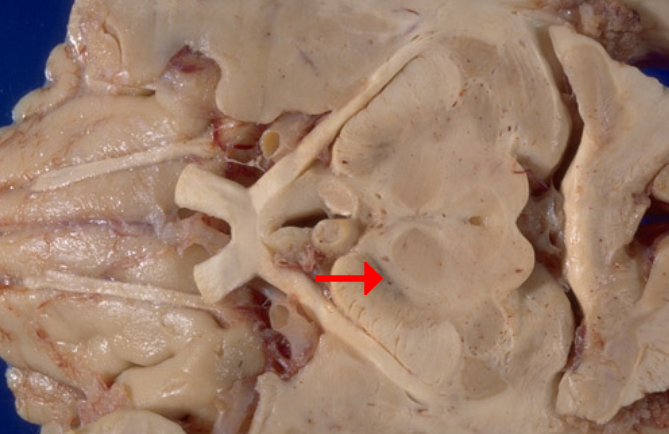

Label this cranial nerve

Olfactory (CN I) nerve

Label this cranial nerve

Optic (CN II) nerve

Label this cranial nerve

Oculomotor (CN III) nerve

Label this cranial nerve

Trochlear (CN IV) nerve

Label this cranial nerve

Trigeminal (CN V) nerve

Label this cranial nerve

Abducens (CN VI) nerve

Label this cranial nerve

Facial (CN VII) nerve

Label this cranial nerve

Vestibulocochlear (VIII) nerve

Label this cranial nerve

Glossopharyngeal (CN IX) nerve

Label this cranial nerve

Vagus (CN X) nerve

Label this cranial nerve

Accessory (CN XI) nerve

Label this cranial nerve

Hypoglossal (CN XII) nerve